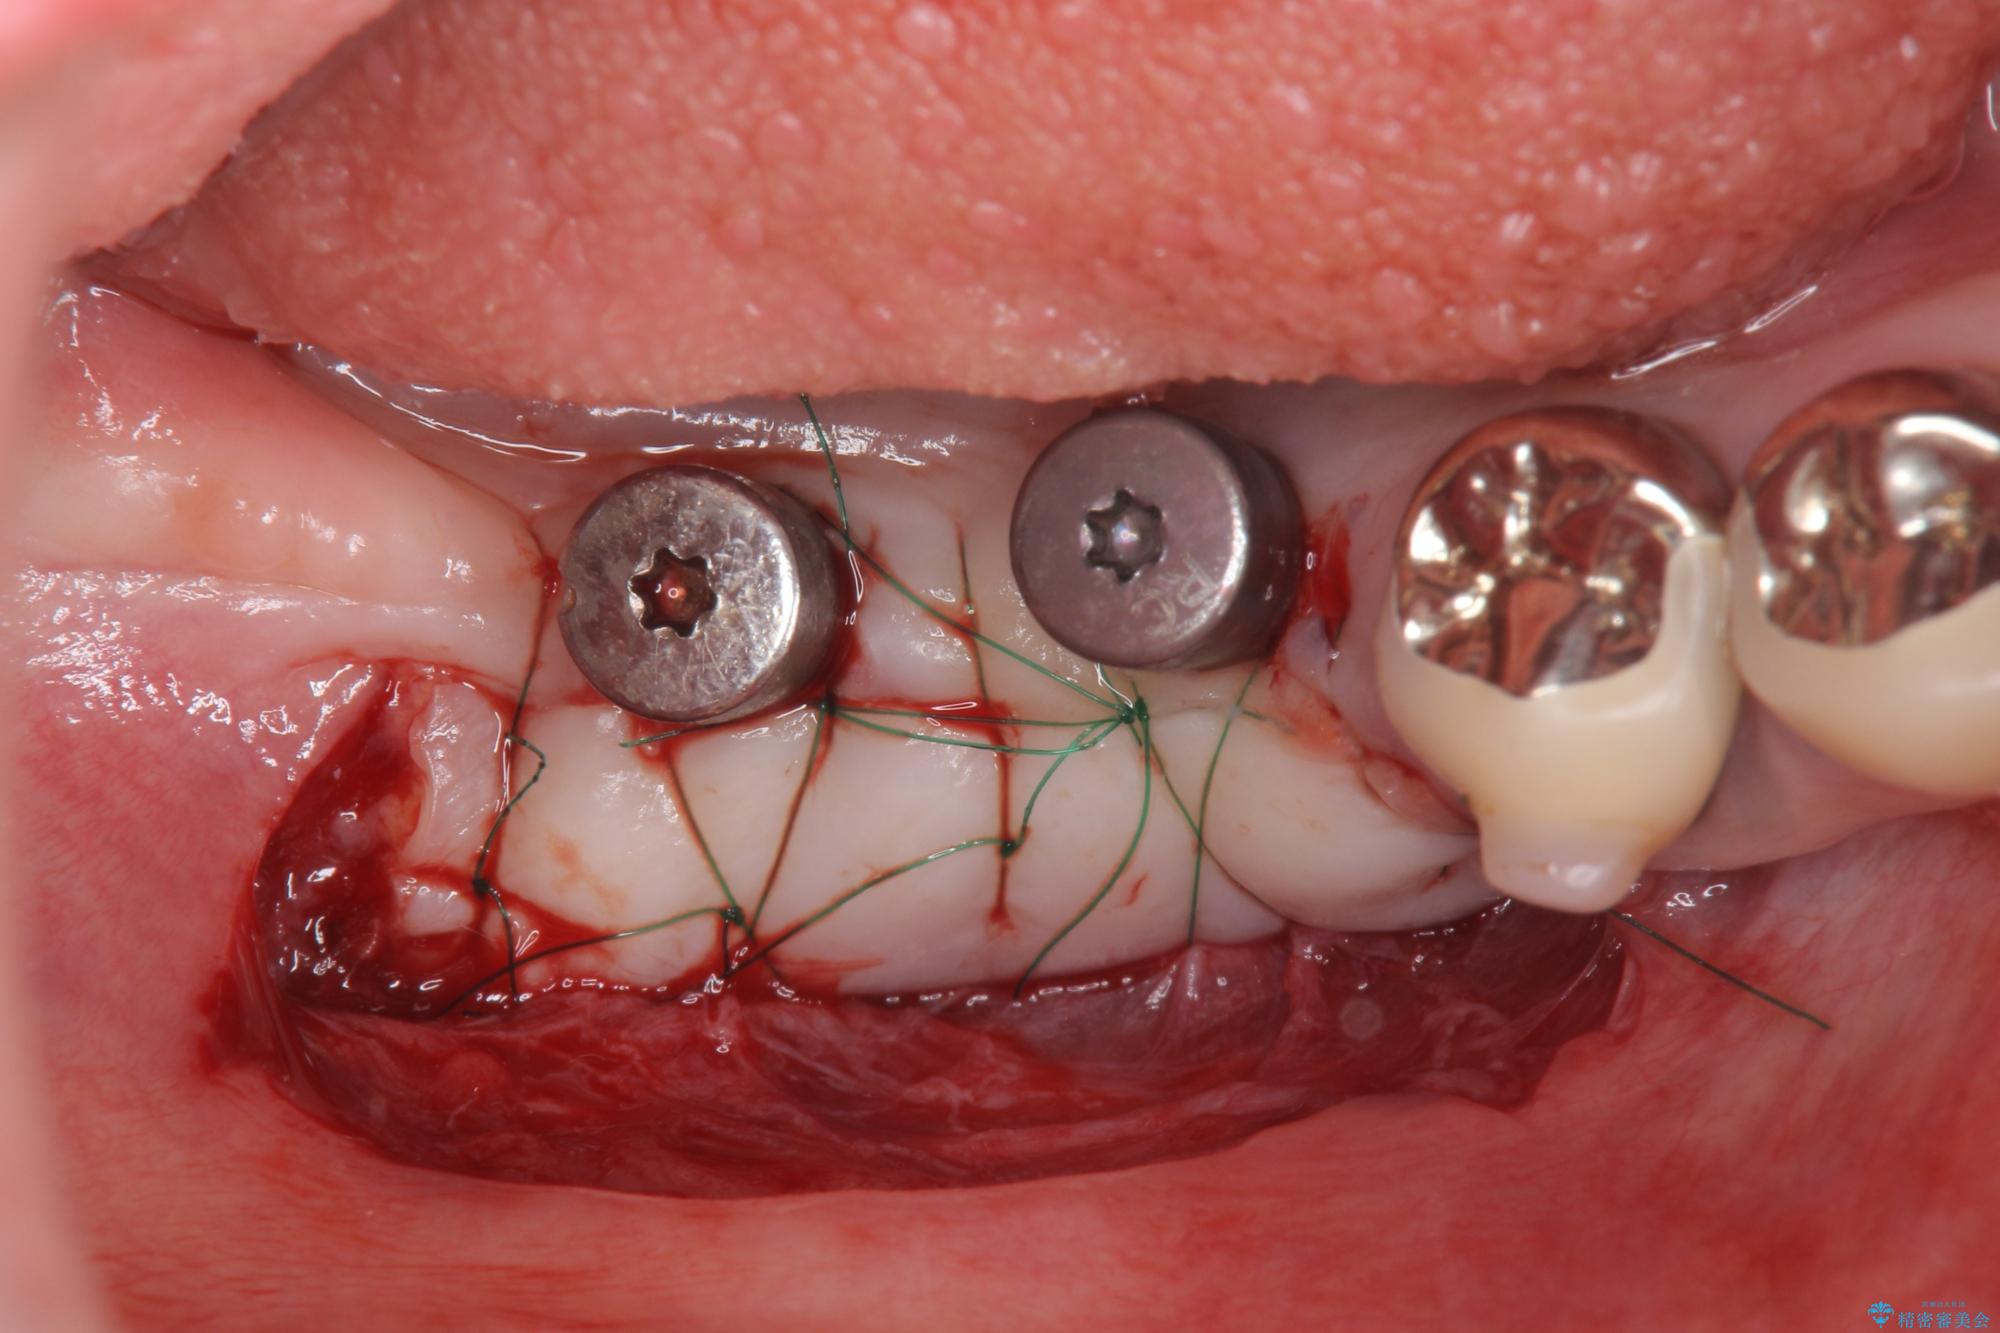

治療中

遊離歯肉移植術を伴うインプラント治療 治療中画像 遊離歯肉移植術を伴うインプラント治療 治療中画像 遊離歯肉移植術を伴うインプラント治療 治療中画像 遊離歯肉移植術を伴うインプラント治療 治療中画像 遊離歯肉移植術を伴うインプラント治療 治療中画像 遊離歯肉移植術を伴うインプラント治療 治療中画像